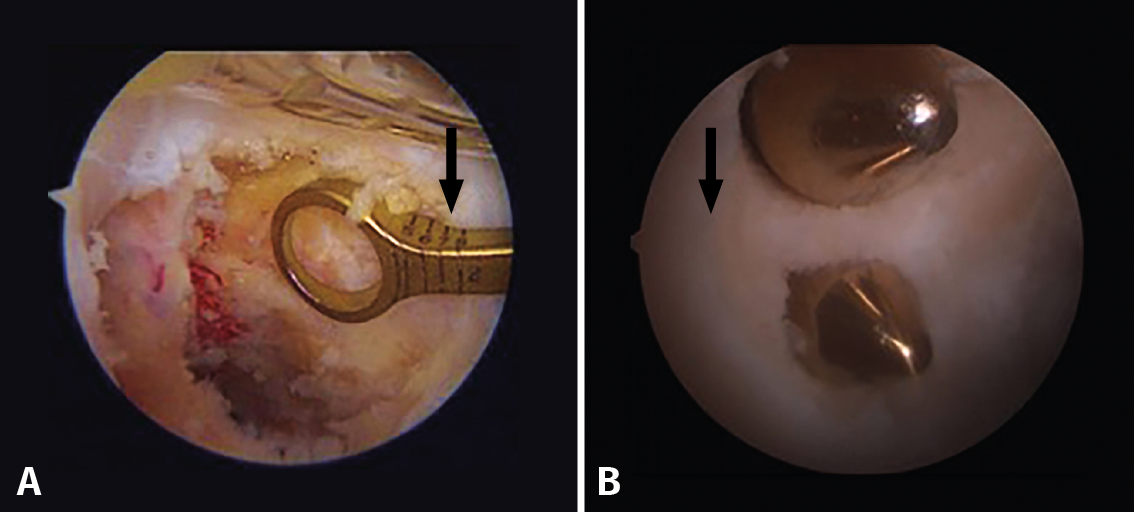

The anatomical references for arthroscopically recognizing the tibial insertion site of the PCL are the most posterior and lateral fibers of the posterior horn of the medial meniscus (Figure 10), defined as shining white fibers that delimit the insertion site medially, and the fibers of the popliteus muscle that indicate the distal margin (27).

Figure 10. A: view from a transpatellar (Gillquist) portal. From the posteromedial working portal we use radiofrequency to clean the tibial insertion site of the posterior cruciate ligament (PCL) which is located in the posterolateral zone of the posterior root of the medial meniscus (arrow); B: view from a posteromedial portal. Fully cleaned tibial insertion site with the arrow indicating the posterior root of the medial meniscus.